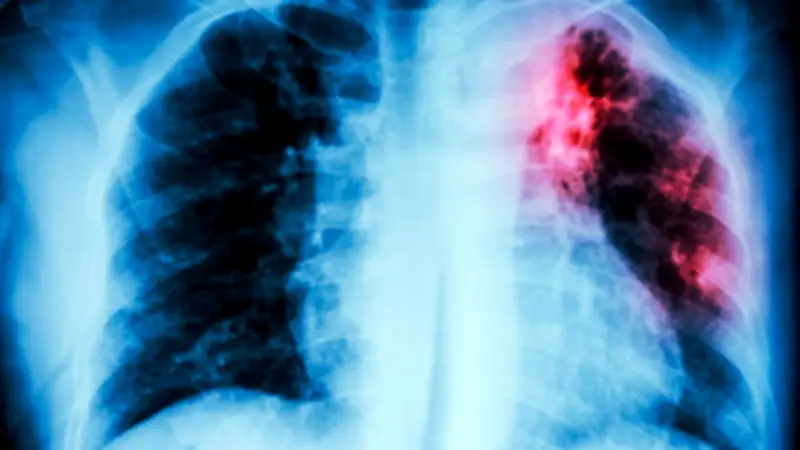

Die Krankheit überträgt sich hauptsächlich über die Luft. Hauptsymptom ist Husten, dazu können Brustschmerzen und Appetitverlust kommen. Die Bakterien können neben der Lunge auch andere Organe befallen. Ohne Behandlung führt eine Tuberkulose-Erkrankung laut WHO-Daten bei etwa jedem zweiten Betroffenen zum Tod.